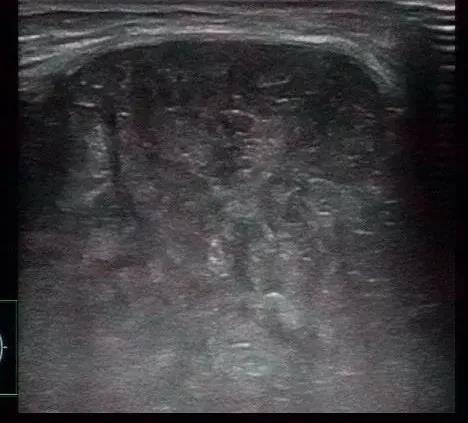

交界性叶状肿瘤:女,63,边界清,肿块大,分叶状,假包膜,裂隙状无回声及条索状高回声,血流稍丰富,结合年龄和超声表现符合叶状肿瘤。